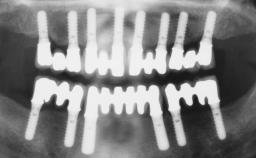

Conventional Loading of Eight Implants in the Maxilla and Final Restoration with a Full-Arch Gold-Ceramic FDP

# of Implants 8

Type of Implants One-Piece

Attachment One-Piece